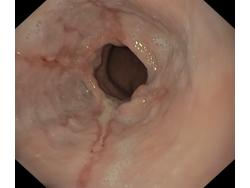

Choroba refluksowa